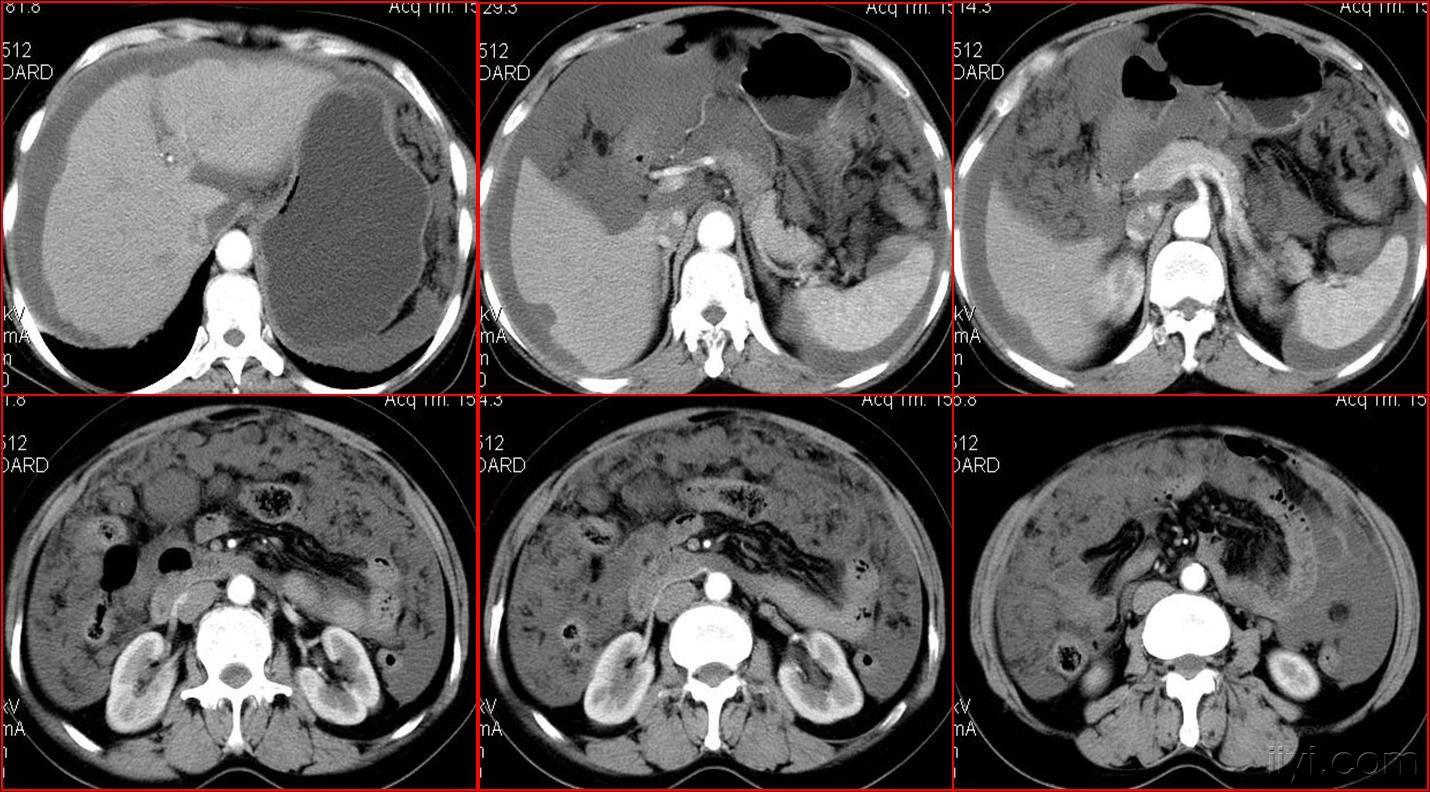

典型的大网膜,肠系膜转移瘤,很经典

图2a大网膜成饼状(ct腹腔横断图象上出现肠曲被前面及两侧的肿瘤组织